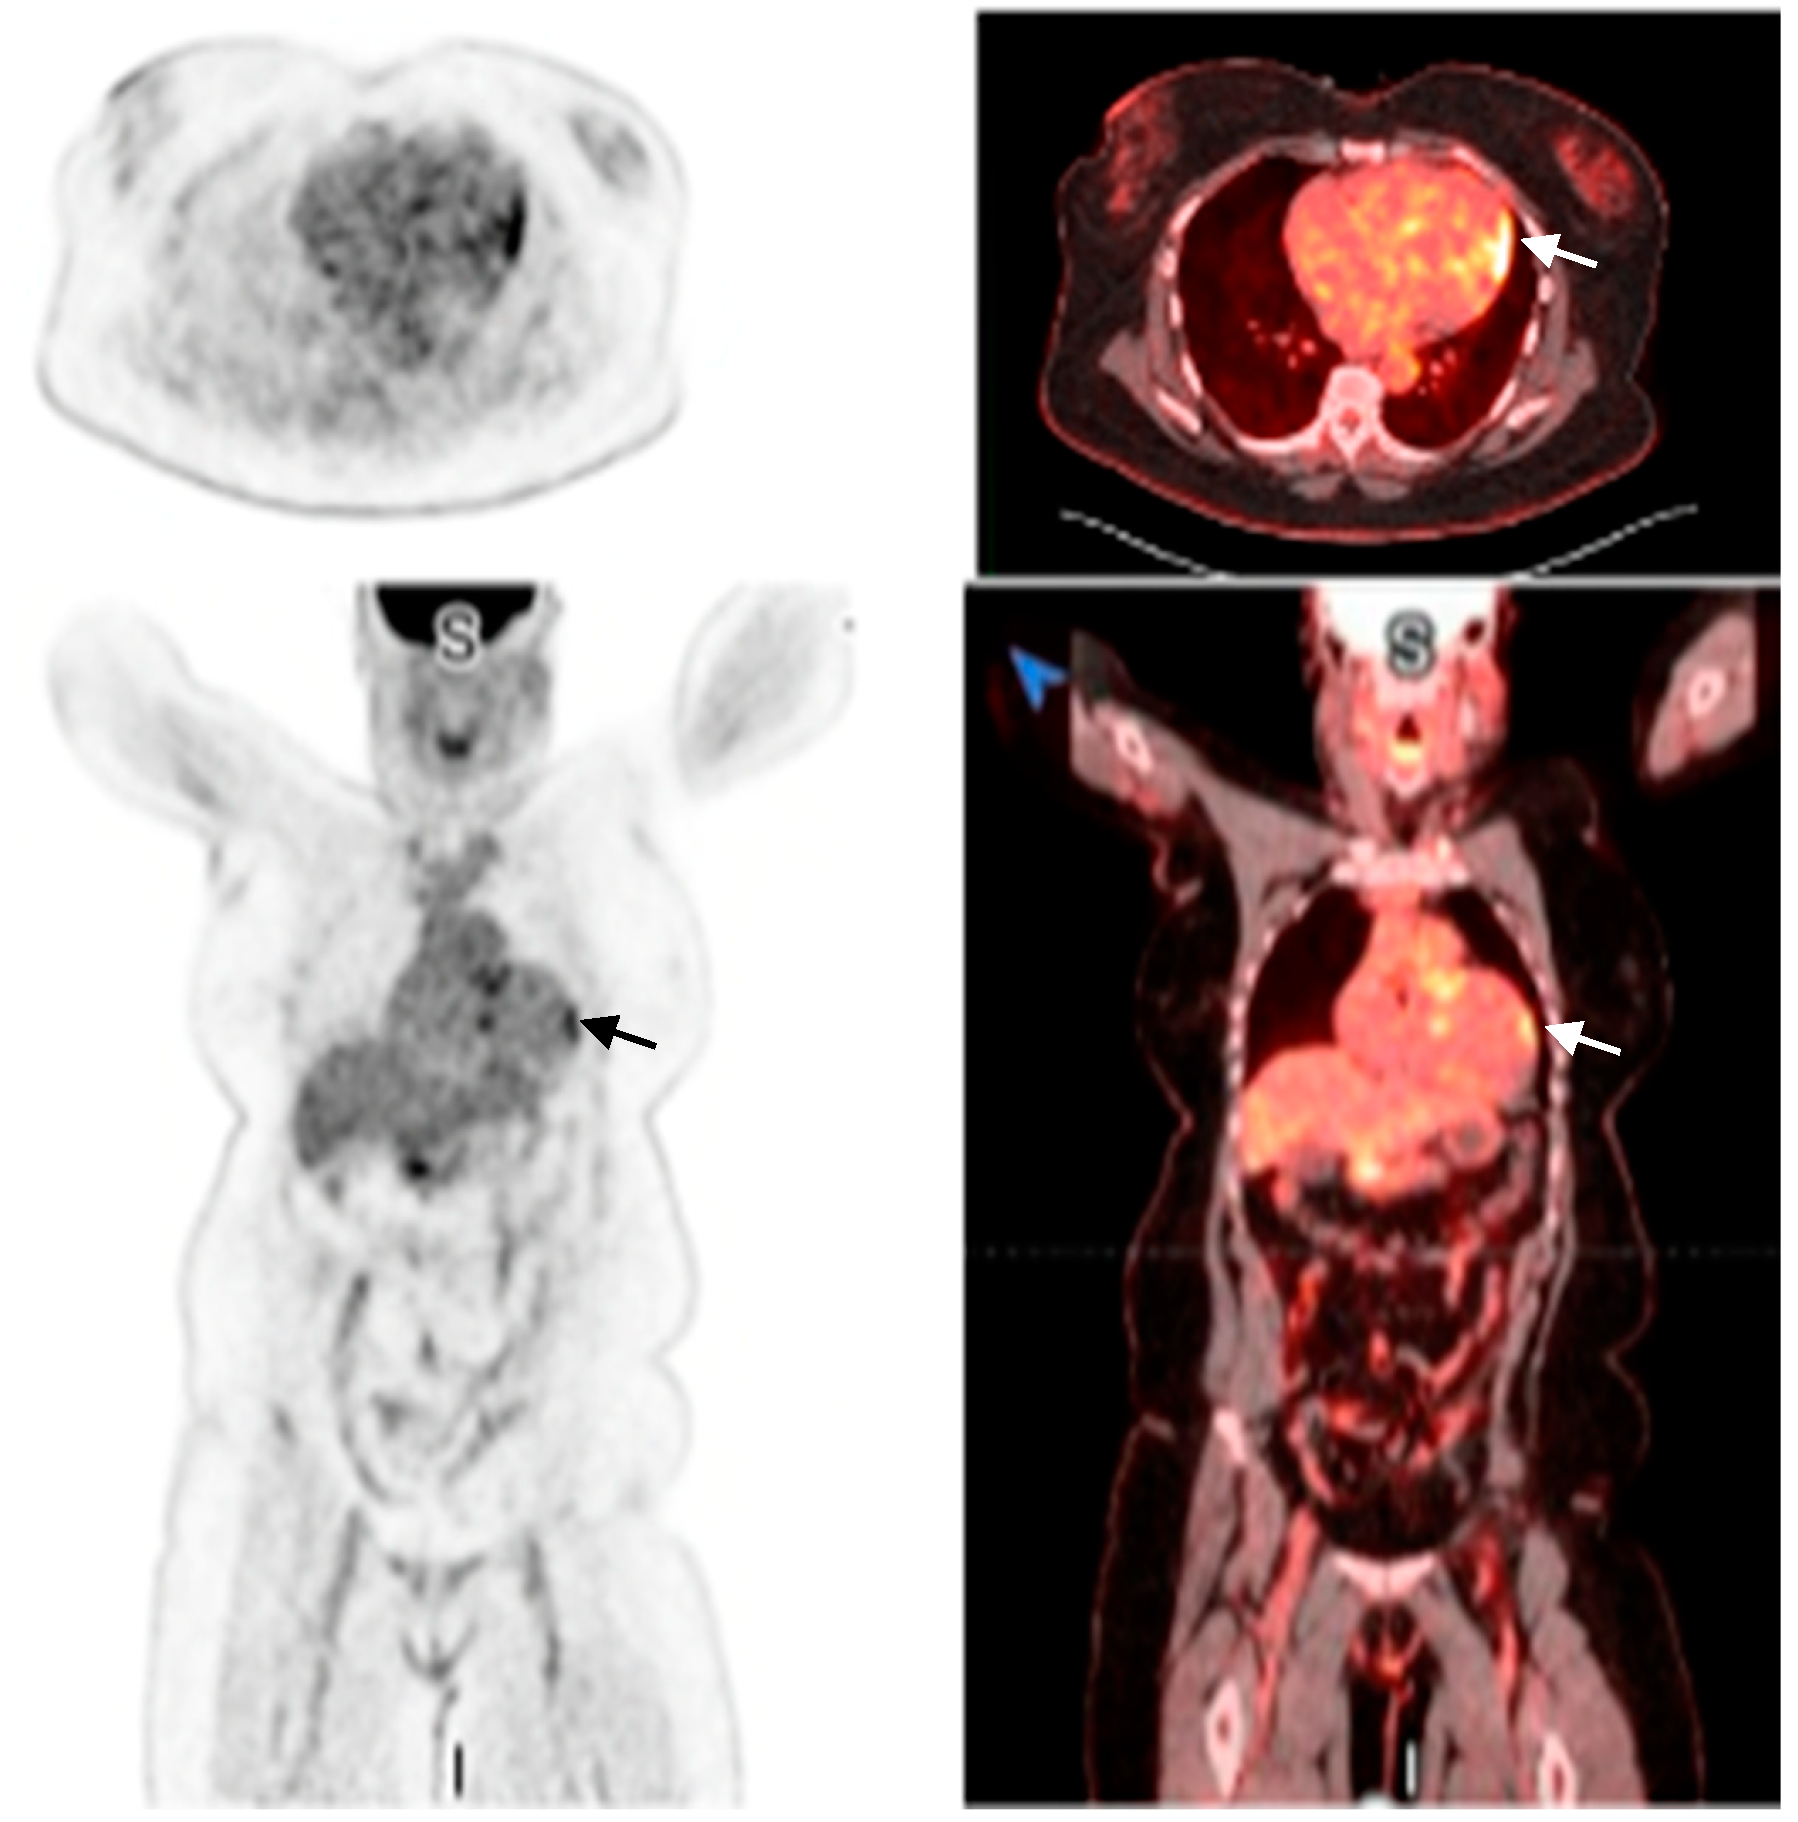

2. Case Presentation

2.1. Investigations

| 13 September 2024 | PET shows >90% probability of cardiac sarcoidosis |